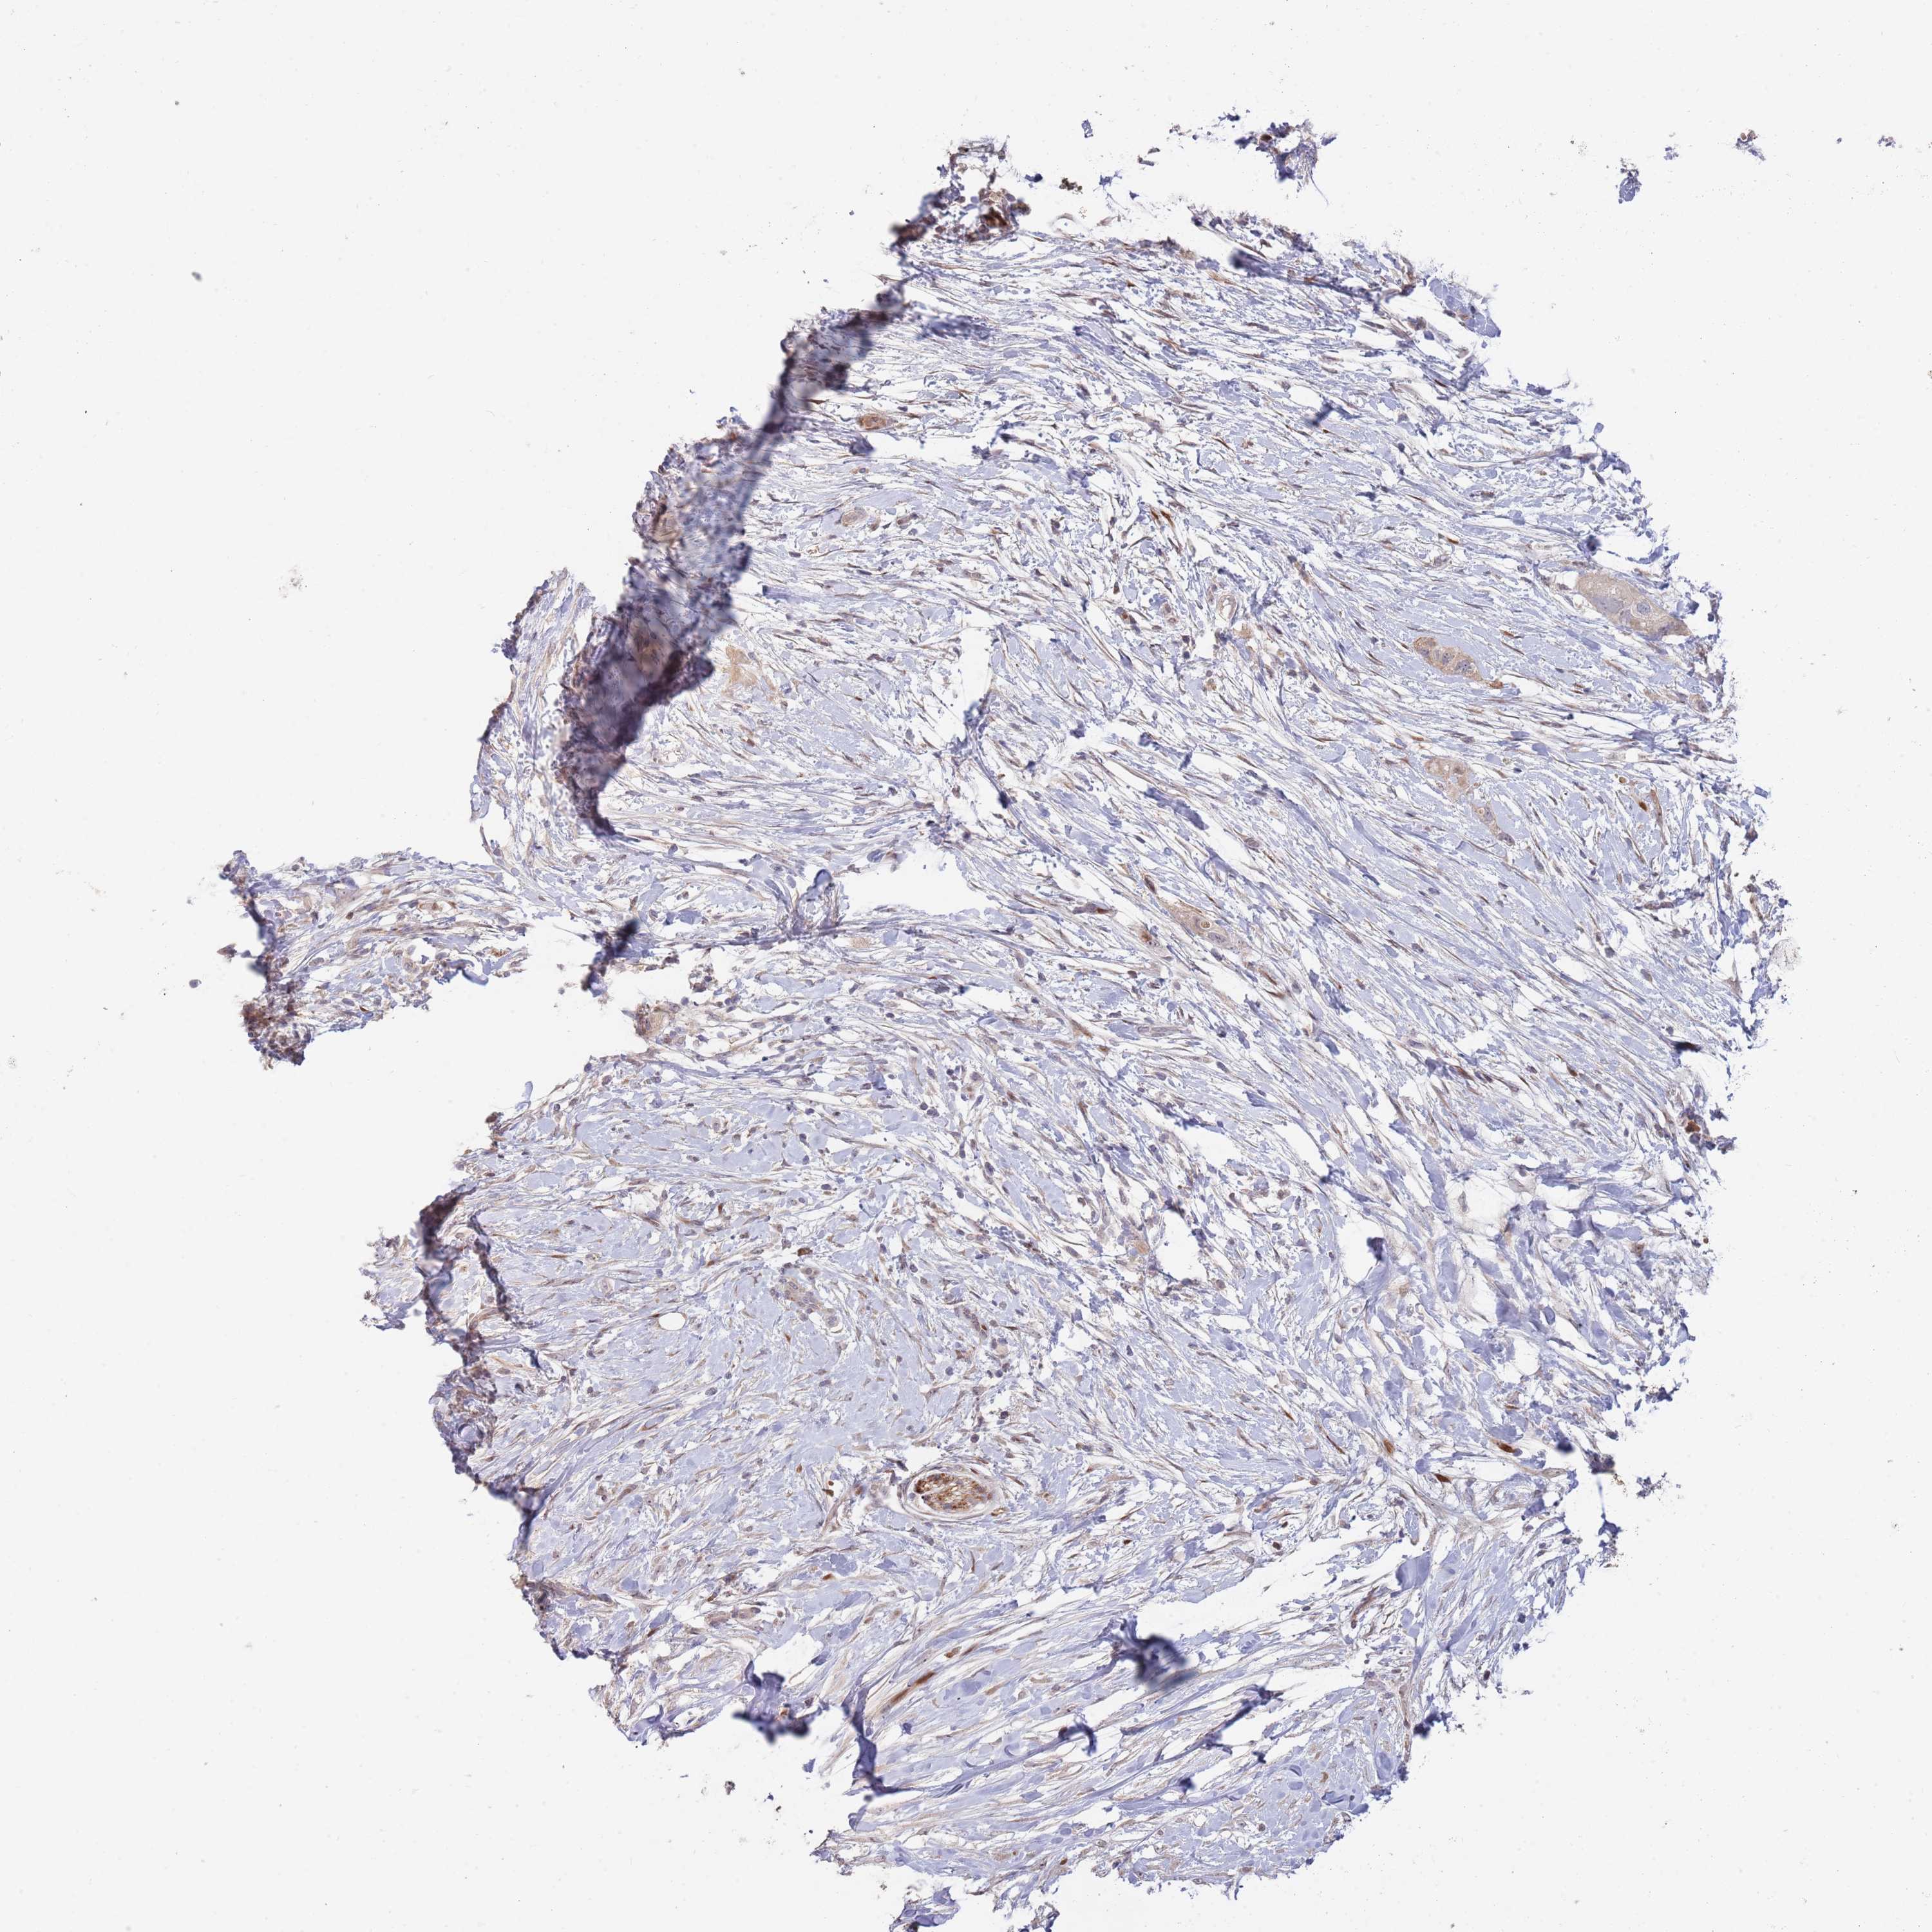

PANCREATIC CANCER - Protein expressioni

A mouse-over function shows sample information and annotation data. Click on an image to view it in a full screen mode. Samples can be filtered based on level of antibody staining by selecting one or several of the following categories: high, medium, low and not detected. The assay and annotation is described here.

Note that samples used for immunohistochemistry by the Human Protein Atlas do not correspond to samples in the TCGA dataset.

Antibody stainingi

Antibody staining in the annotated cell types in the current human tissue is reported as not detected, low, medium, or high, based on conventional immunohistochemistry profiling in selected tissues. This score is based on the combination of the staining intensity and fraction of stained cells.

Each image is clickable and will lead to virtual microscopy that enables deeper exploration of all samples and also displays staining intensity scores, fraction scores and subcellular localization as well as patient and tissue information for each sample.

Antibody HPA042594

Antibody HPA048487

Adenocarcinoma, NOS